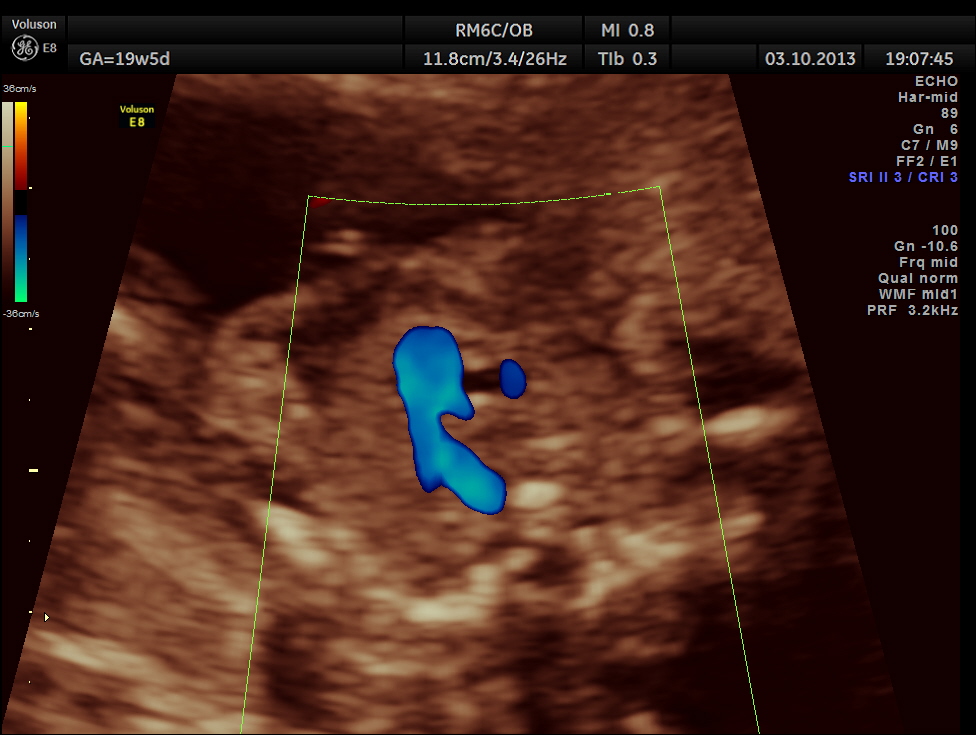

The following pictures show that the left ventricle appears smaller than the right ventricle. The situs is normal.

Colour flow also rules out the possibility of hypoplastic left heart syndrome.